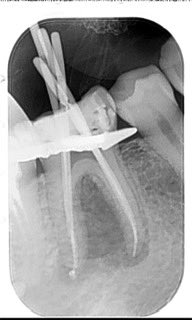

Re-RCT #46

Previously treated & chronic apical abscess.

Pus was drained through the canals, instrumentation was done, intra-canal medication and follow-up.

After 2 weeks the patient came and the buccal expansion is reduced, heavy irrigation was done then obturation 👍